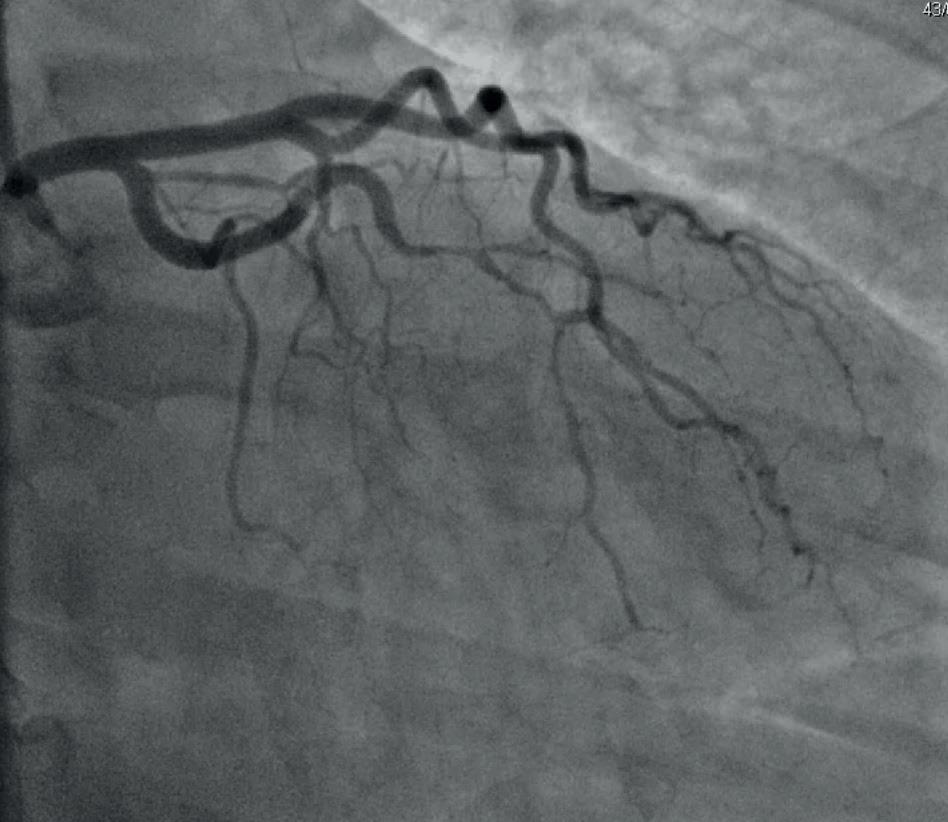

Spontan koronararteriedisseksjon (SCAD) er en ikke-aterosklerotisk årsak til akutt koronart syndrom som oppstår når en spontan intramural blødning medfører separasjon av intima fra underliggende karsegment i koronararterieveggen (1). Iskemi og akutt myokardinfarkt oppstår når hematomdannelse i tunica media (falsk lumen) obstruerer ekte lumen (2), som demonstrert i figur 1.

Prevalens, diagnose og behandling SCAD-forekomst er rapportert hos mellom 1-4 % av pasienter som gjennomgår selektiv koronar angiografi for akutt koronart syndrom. Diagnosen er vanlig hos kvinner som angiograferes for akutt koronart syndrom under 60 år (5).

Diagnosen SCAD settes ved selektiv koronarangiografi. Det finnes tre angiografiske typer ifølge Yip-Sawklassifisering: type 1, type 2 og type 3 (11), som illustrert i figur 3. Type I karakteriseres ved kontrastpenetrasjon over i falsk lumen som noen ganger gir et dobbel lumenutseende. Type II ser ut som diffus stenose av ulik grad som i noen tilfeller viser distal utbredelse. Dette er den mest vanlige formen. Type III ligner på vanlig aterosklerose og betegnes som «mimicker» og kan være utfordrende å diagnostisere. Lengde av lesjonen som vanligvis er mellom 11-20 mm, er patognomonisk for SCAD (12). Behovet for intrakoronar bildefremstilling i form av intravaskulær ultralyd (IVUS) eller optisk koherenstomografi (OCT) er større ved type III-SCAD grunnet diagnostisk utfordring.